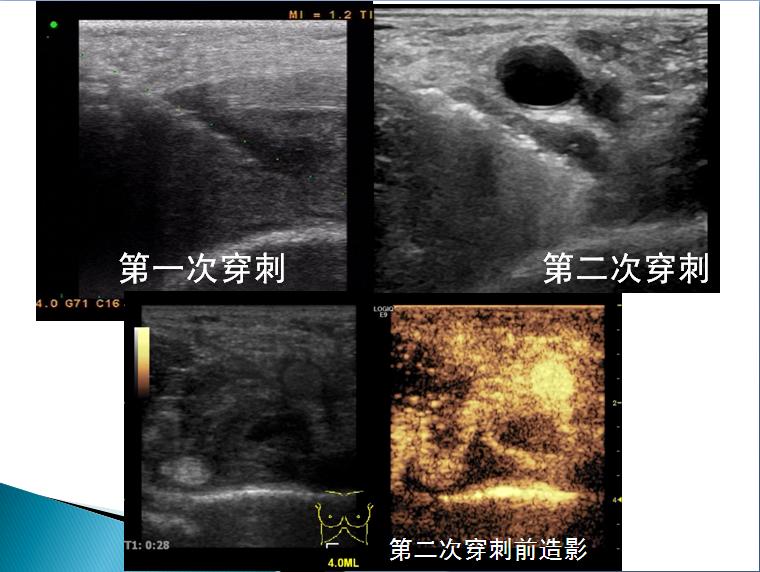

第三届中国超声造影大会病例大赛北医三院超声科获奖病例展示(五)